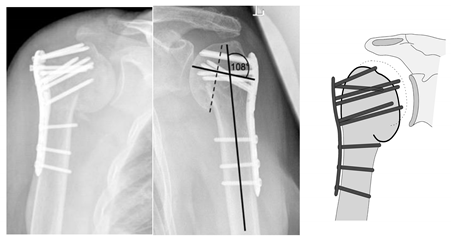

| Complication Type | Exemplary Images by X-rays or Pattern Images | Definition |

|---|---|---|

| 4 | ![]() | Complication Type 4a is based on the presence of AVN of the humeral head without concomitant destruction of the glenoid articular surface due to an associated screw cutout through the humeral head cortex. |

| 4b | ![]() | Complication Type 4b is also based on the presence of an AVN of the humeral head combined with a destruction of the glenoid articular surface due to the associated screw cutout through the humeral head cortex. |